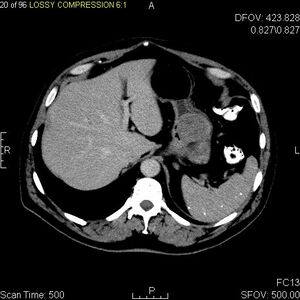

لتشخيص الأورام السدية المعدية المعوية غالباً ما يُجرى التصوير المقطعي المحوسب (انظر قسم علم الأشعة). إن الصبغة الكيميائية النسيجية المناعية للبيتا-كاتينين في نوى الخلايا هو نتيجة ثابتة في الأورام الليفية الرحمية، ويساعد في التمييز بين مثل هذه الأورام وأورام الخلايا المغزلية الموجبة للبيتا كاتينين.[18]

التصوير الطبي

الغرض من التصوير الإشعاعي هو تحديد موقع الآفة، وتقييم علامات الغزو، والكشف عن النقائل. تختلف سمات الأورام السدية المعدية المعوية باختلاف حجم الورم والعضو المنشأ. يمكن أن يتراوح قطرها من بضعة مليمترات إلى أكثر من 30 سم. عادةً ما تُسبب الأورام الأكبر أعراضاً، على عكس تلك التي تُكتشف بالصدفة، والتي عادةً ما تكون أصغر حجماً وذات تشخيص أفضل.[4][20] تميل الأورام الكبيرة إلى إظهار سلوك خبيث لكن الأورام السدية المعدية المعوية الصغيرة قد تظهر أيضاً سلوكاً عدوانياً سريرياً.[21]

تُستخدم فحوصات الباريوم الفلوري والتصوير المقطعي المحوسب عادةً لتقييم المرضى الذين يعانون من مشاكل في البطن. تُظهر صور الباريوم الفلوري وجود تشوهات في 80% من حالات الأورام السدية المعدية المعوية.[21] مع ذلك، قد تحدث بعض الأورام السدية المعدية المعوية خارج تجويف الأمعاء تماماً، ولا يُمكن تشخيصها بفحص الباريوم. حتى في الحالات التي يكون فيها فحص الباريوم غير طبيعي، يجب إجراء تصوير بالرنين المغناطيسي أو التصوير المقطعي المحوسب، إذ يستحيل تقييم تجاويف البطن وأعضاء البطن الأخرى بفحص الباريوم وحده. في التصوير المقطعي المحوسب، قد تُلاحظ تشوهات لدى 87% من المرضى، ويجب إجراؤه باستخدام مادة تباين فموية وريدية.[21] من بين دراسات التصوير، يُعدّ التصوير بالرنين المغناطيسي أفضل تباين للأنسجة، مما يُساعد في تحديد الكتل داخل الجهاز الهضمي (الكتل داخل الجدار). يلزم حقن مادة تباين وريدية لتقييم الأوعية الدموية في الآفة.

طرق التصوير المفضلة في تقييم الأورام السدية المعدية المعوية هي التصوير المقطعي المحوسب والتصوير بالرنين المغناطيسي،[23] وفي حالات معينة، الموجات فوق الصوتية بالمنظار. تشمل مزايا التصوير المقطعي المحوسب قدرته على إظهار أدلة على غزو الأعضاء المجاورة، والاستسقاء، والنقائل. كما أن قدرة التصوير بالرنين المغناطيسي على إنتاج صور في مستويات متعددة تُساعد في تحديد الأمعاء كعضو منشأ (وهو أمر صعب عندما يكون الورم كبيراً جداً)، مما يُسهّل التشخيص.

مع نمو الورم، قد يبرز خارج الأمعاء (نمو خارجي) و/أو داخلها (نمو داخل التجويف)، لكن في أغلب الأحيان ينمو الورم خارجياً بحيث يبرز الجزء الأكبر منه في تجويف البطن. إذا تجاوز الورم إمداده الدموي، فقد ينخر داخلياً، مكوّناً تجويفاً مركزياً مملوءاً بالسوائل مع نزيف وتجويفات قد تتقرح في النهاية وتتصل بتجويف الأمعاء. في هذه الحالة، قد يُظهر فحص الباريوم وجود هواء، أو مستويات هواء-سوائل، أو تراكماً لوسائط التباين الفموية في هذه المناطق.[21][25] قد تظهر أيضاً تقرحات مخاطية. في صور الأشعة المقطعية المحسنة بالتباين، تظهر أورام الجهاز الهضمي المعدية الكبيرة ككتل غير متجانسة بسبب وجود مناطق من خلايا الورم الحية المحيطة بالنزيف أو النخر أو الأكياس، والتي تُرى شعاعيًا كنمط تعزيز محيطي بمركز توهين منخفض.[20] في دراسات التصوير بالرنين المغناطيسي، تؤثر درجة النخر والنزيف على نمط شدة الإشارة. تختلف شدة الإشارة في مناطق النزيف داخل الورم تبعًا لتاريخ حدوث النزيف. عادةً ما تكون شدة الإشارة في الأجزاء الصلبة من الورم منخفضة في صور الرنين المغناطيسي الموزونة بـ T1، وتكون شدة الإشارة فيها عالية في صور الرنين المغناطيسي الموزونة بـ T2، وتزداد بعد إعطاء الگادولينيوم. توجد فراغات ذات شدة إشارة في حال وجود غاز داخل مناطق الورم النخرية.[22][26][27]

تتميز الأورام الخبيثة بالغزو الموضعي والانتشار، عادةً إلى الكبد، والثرب، والصفاق. ومع ذلك، فقد لوحظت حالات انتشار الورم إلى العظام، والتجويف الجنبي، والرئتين، وخلف الصفاق. بخلاف السرطانة الغدية المعدية أو سرطان الغدد اللمفاوية في المعدة/الأمعاء الدقيقة، فإن تضخم العقد الليمفاوية الخبيث نادر (<10%)، وبالتالي يُظهر التصوير عادة غياب تضخم العقد الليمفاوية.[20] إذا لم تكن النقائل موجودة، فإن السمات الشعاعية الأخرى التي تشير إلى الخباثة تشمل: الحجم (>5 سم)، والتعزيز غير المتجانس بعد إعطاء التباين، والتقرحات.[4][20][28] كما أن السلوك الخبيث الواضح (على النقيض من احتمالية الخباثة بدرجة أقل) أقل شيوعاً في أورام المعدة، حيث تبلغ نسبة من السلوك الحميد إلى السلوك الخبيث الواضح تتراوح بين 3-5.[4] حتى لو كانت السمات الخبيثة الشعاعية موجودة، فإن هذه النتائج قد تمثل أيضاً أوراماً أخرى ويجب إجراء التشخيص النهائي كيميائياً مناعياً.